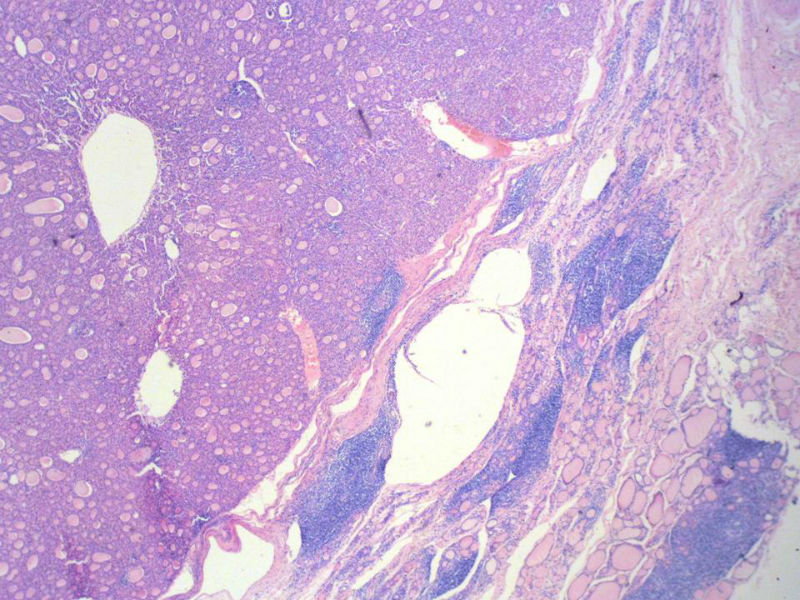

女,60岁,右侧甲状腺肿物两个月,术中见肿块与周围组织无粘连,肉眼,灰红色组织,3X2X2厘米,切面见一直径2.5厘米肿物,包膜完整,灰黄色,质软。

右侧甲状腺肿物图3

名称:图3

具有桥本氏病的大部分特征,有结节形成,此情况有称之为“结节性桥本甲状腺炎”